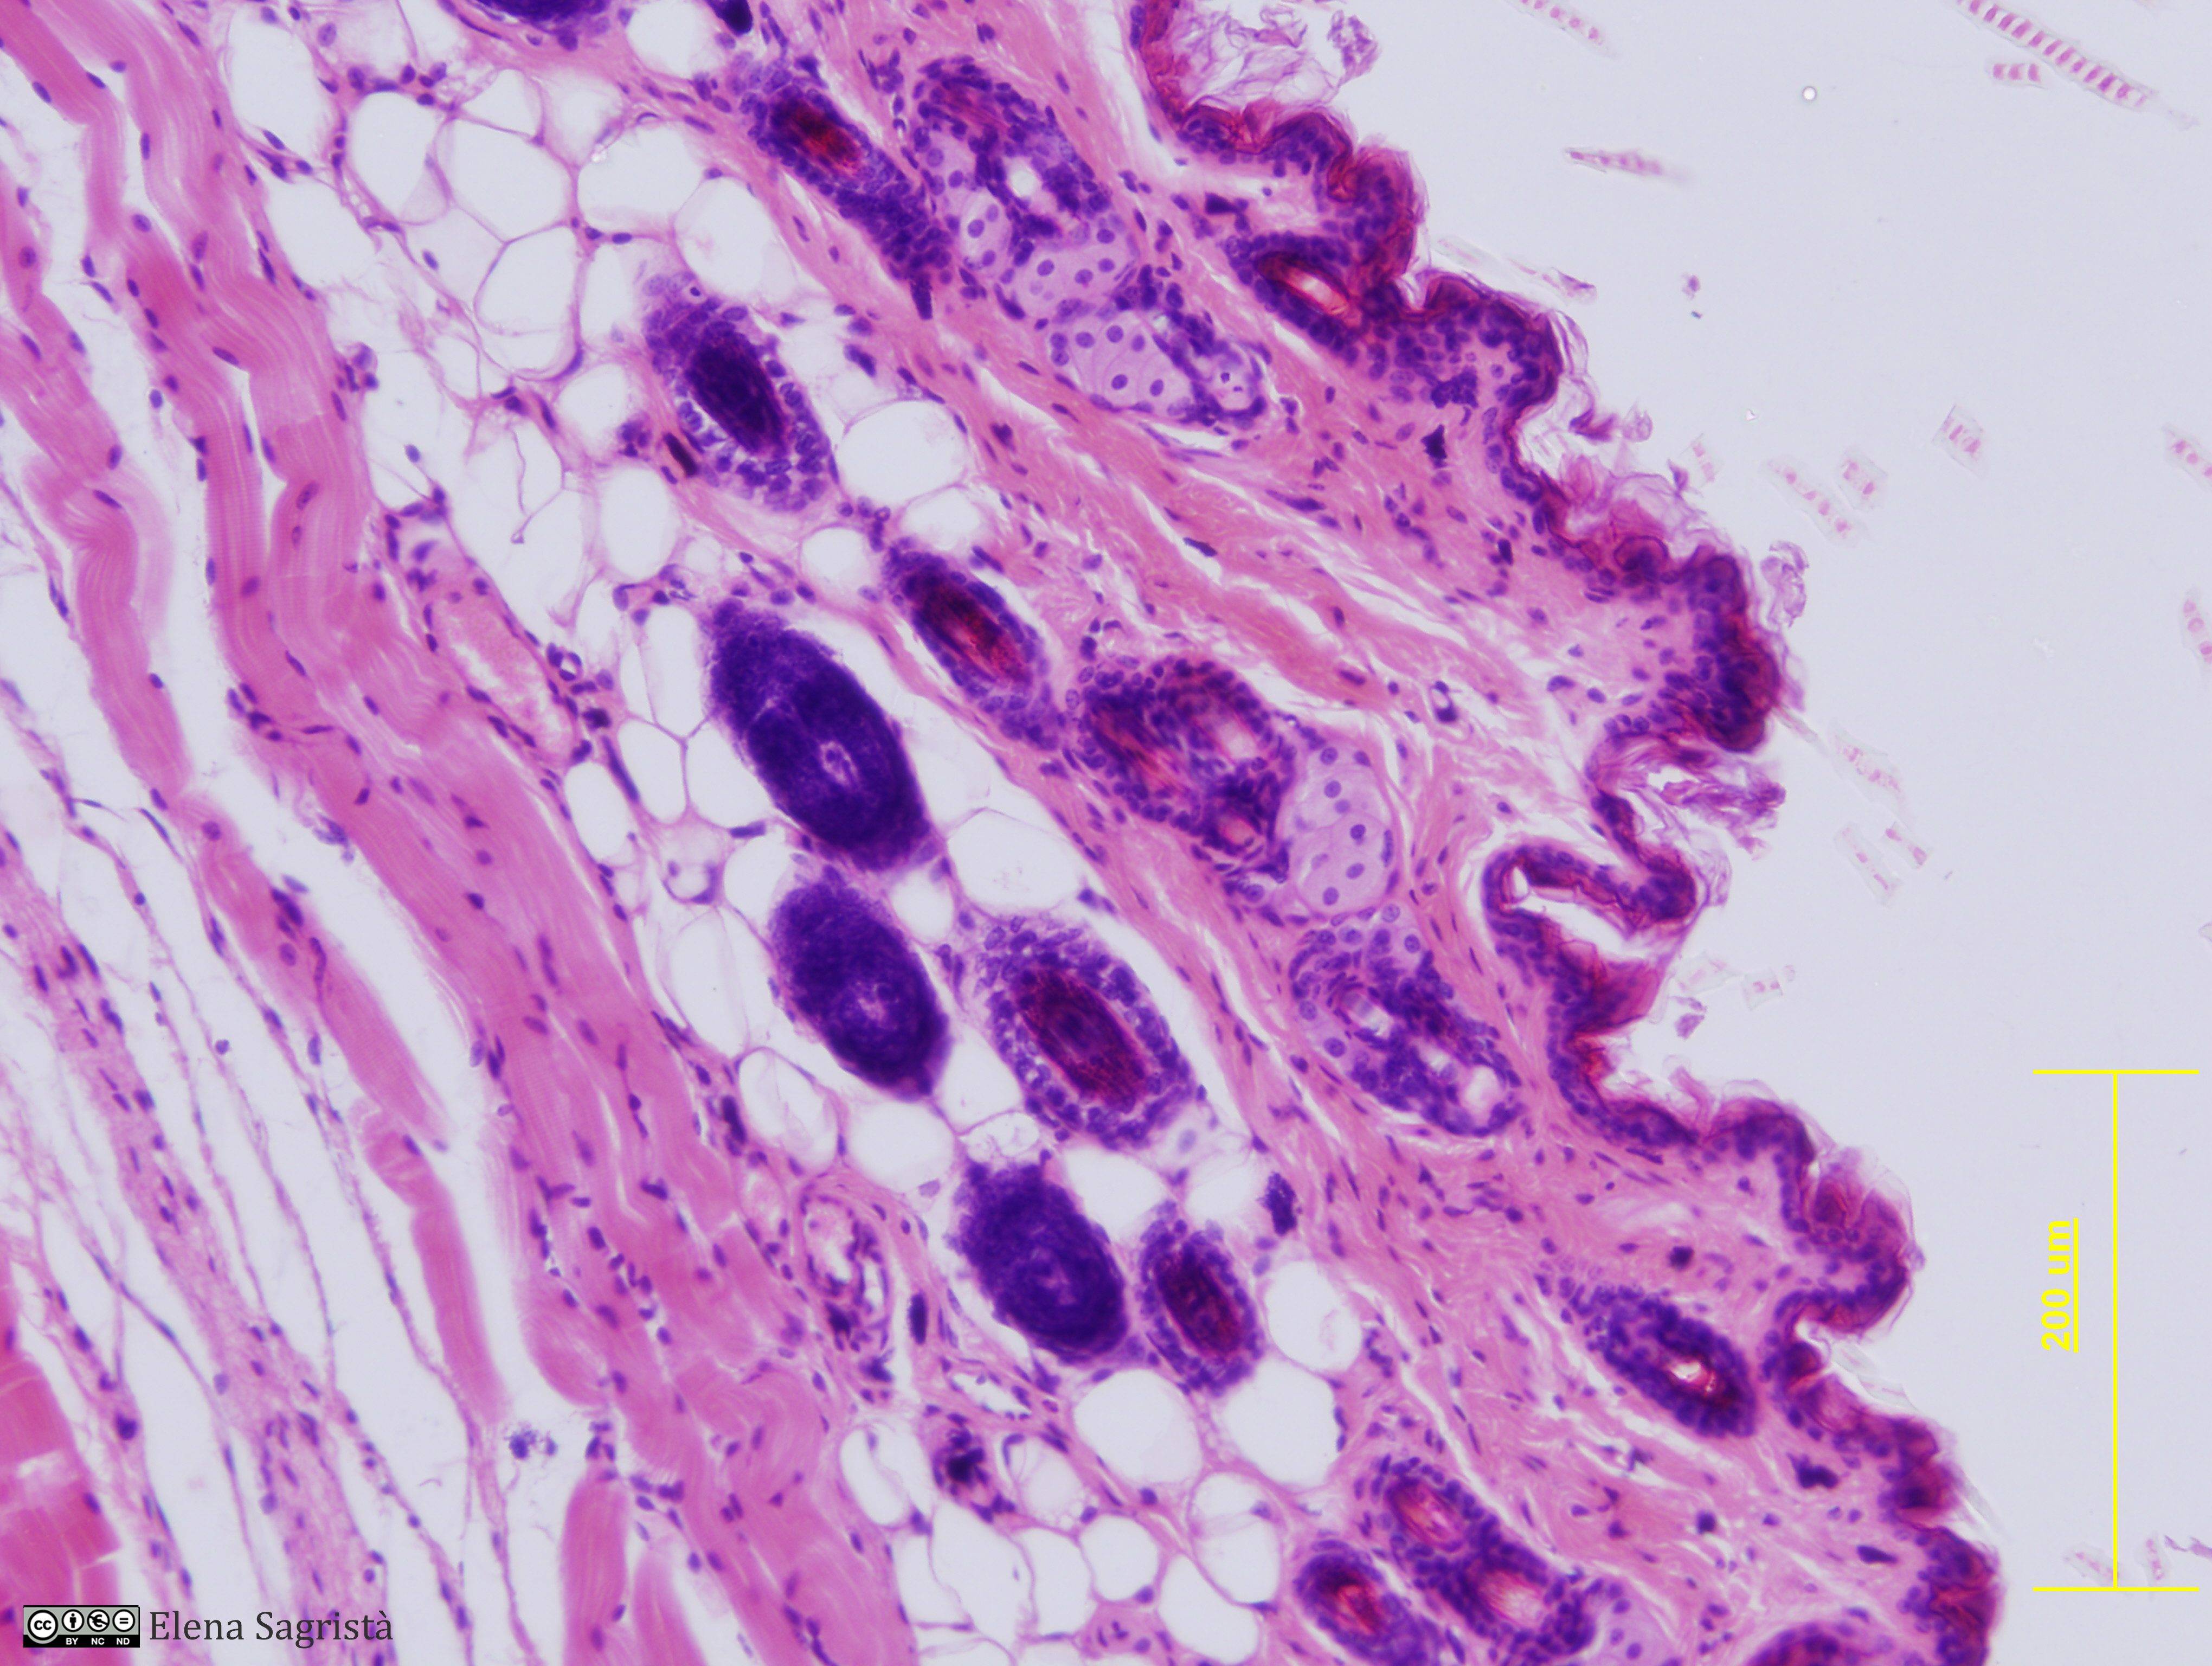

Histologia imatges: 11 Pell

Imatges de preparacions histològiques de Pell. Microscopia òptica.